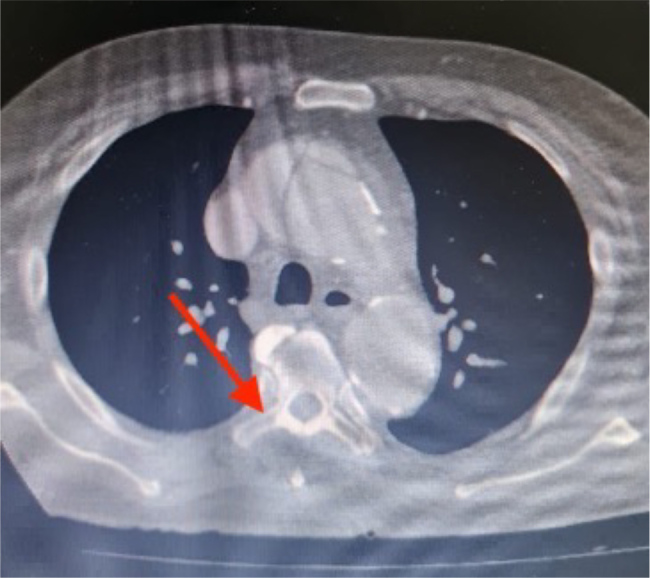

Aortic dissection is a life-threatening cardiovascular emergency, particularly Stanford type A, which typically necessitates urgent surgical intervention. Despite advances in surgical techniques and perioperative care, preoperative bleeding and coagulopathy remain significant challenges. Tranexamic acid, an antifibrinolytic agent, is widely used to minimize perioperative bleeding in cardiovascular surgeries; however, its role in the non-surgical, preoperative stabilization of aortic dissection has not been well established. We present the case of a 56-year-old woman with a history of hypertension and dyslipidaemia who presented with sudden-onset, severe interscapular chest pain. Computed tomography angiography revealed an ascending aortic dissection. Initial management included intravenous labetalol for blood pressure and heart rate control, along with the administration of 1 gram of tranexamic acid. She was subsequently transferred for emergent surgical repair. Intraoperatively, however, no active aortic bleeding was identified. Instead, a clot was found sealing the dissected segment of the ascending aorta, effectively halting further propagation and haemorrhage. This unexpected finding led to the cancellation of surgical repair. We hypothesize that tranexamic acid contributed significantly to the formation of this stabilizing clot through its antifibrinolytic effects. The patient's clinical outcome was favourable, with no complications observed. This case highlights a novel potential application of tranexamic acid in the emergency management of aortic dissection. To our knowledge, this is the first reported case in which tranexamic acid contributed to spontaneous thrombus formation within a dissected aortic segment, preventing catastrophic haemorrhage and obviating the need for surgery.

Learning points: This case highlights a potentially important role for tranexamic acid (TXA) in the management of aortic dissection. To our knowledge, this is the first reported case of its kind.While its established use in reducing postoperative bleeding and transfusion requirements is well documented, our case demonstrates a preoperative benefit, with TXA contributing to the formation of a stabilizing thrombus within the dissected aortic segment.This life-saving clot prevented further dissection and haemorrhage, ultimately deferring the need for surgical repair and reducing the risk of perioperative complications.We aim to underscore the need for further investigation into the potential role of tranexamic acid in the acute management of aortic dissection.